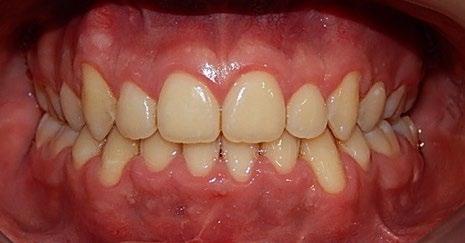

En los estudios intraorales, las fotografías iniciales muestran clase I canina y molar bilateral, mordida anterior abierta, apiñamiento leve superior e inferior, y líneas medias dentales

desviadas. En las Figuras 4, 5 y 6 se observa la forma de las arcadas superior e inferior.

Figura 4. Lateral derecha.

Figura 5. Intraoral de frente e izquierda.

Figura 6. Oclusal superior e inferior de inicio.